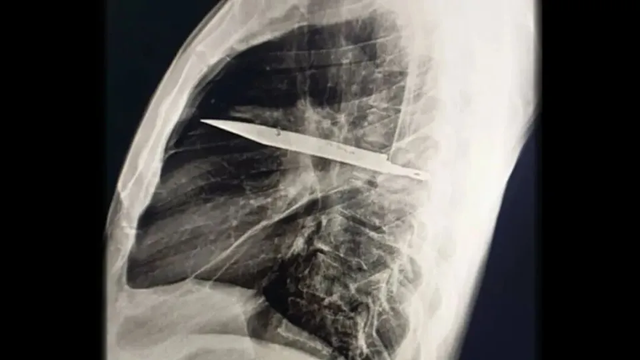

Khi thăm khám, bác sĩ nhận thấy ngực phải của bệnh nhân không nở ra đầy đủ khi hít vào, kèm theo lỗ rò rỉ dịch mủ có mùi hôi. Kết quả chụp X-quang khiến toàn bộ ê-kíp choáng váng: một lưỡi dao lớn gãy nằm gọn trong khoang ngực, kéo dài từ vùng xương bả vai phải đến trước xương sườn.

Phim chụp X-quang ngực của bệnh nhân cho thấy một lưỡi dao lớn găm vào giữa lồng ngực